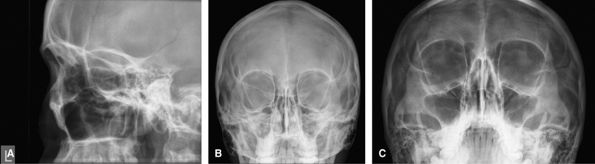

Not used very often because most indications for a skull

radiograph are better served by a CT. Can still be used to assess shunt

continuity.

Figure 44 (A) PA skull. (B) Lateral skull. (C) Townes view.